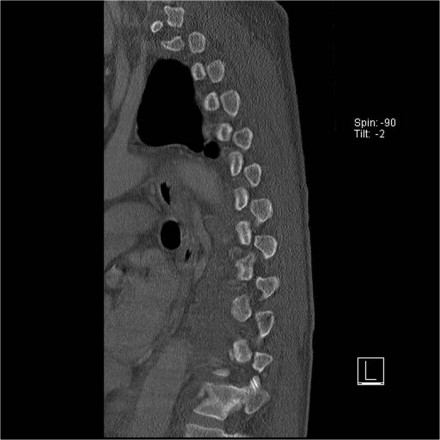

The images are of a patient with a typical bamboo spine as a result of ankylosing spondylitis.

After a fall on his back no fracture was seen on the x-rays.

However the CT shows a thin fracture line through the anterior side of the vertebral body and also through the spinous process.